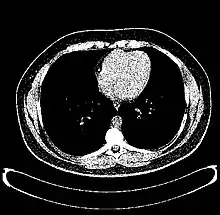

The Hounsfield scale (/ˈhaʊnzfiːld/ HOWNZ-feeld), named after Sir Godfrey Hounsfield, is a quantitative scale for describing radiodensity. It is frequently used in CT scans, where its value is also termed CT number.

Values for different body tissues and material

HU-based differentiation of material applies to medical-grade dual-energy CT scans but not to cone beam computed tomography (CBCT) scans, as CBCT scans provide unreliable HU readings.[4]

Values reported here are approximations. Different dynamics are reported from one study to another.

Exact HU dynamics can vary from one CT acquisition to another due to CT acquisition and reconstruction parameters (kV, filters, reconstruction algorithms, etc.). The use of contrast agents modifies HU as well in some body parts (mainly blood).